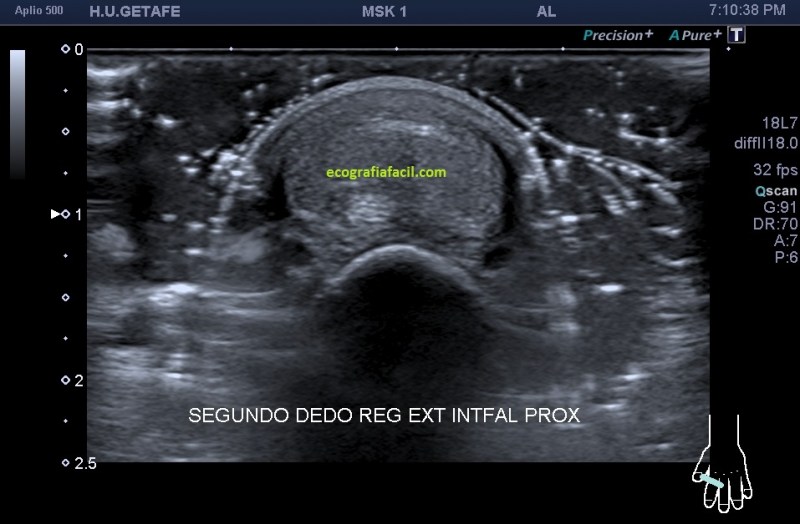

Hoy vas a ver el caso de un paciente que acude por un bulto de largo tiempo de evolución en la región extensora del segundo dedo justo a la altura de la articulación interfalángica proximal. Acude a su médico al observar crecimiento lento y por el volumen, ligera incapacidad a la hora de flexionar y extender el dedo. Es indoloro, aunque por el tamaño, estira la piel, sin llegar a afectarla. Es blando a la palpación.

Exploración ecográfica:

Seguimos en este post a pies juntillas el protocolo en la exploración de bultos, localizar, estudiar, medir y vascularización. Aquí el protocolo se hace más que importante sobre todo en las imágenes de la 1 a la 4 ya que es vital, en estos casos donde las estructuras que participan del estudio son tan pequeñas, saber discernir bien las diferentes ecoestructuras implicadas. Es decir, la localización y el estudio pormenorizado, con la máxima calidad de imagen que podamos conseguir ajustando los parámetros técnicos que te he explicado tantas veces, en este caso fueron definitivos para la calidad del estudio.

El tendón extensor es una ecoestructura muy fina, que puede pasar desapercibida si no tenemos una alta calidad de imagen, en la imagen 4 lo tienes delimitado entre dos líneas rosas, por si en la imagen 3 te había costado situarlo, repito, fundamental en este estudio su caracterización.

La anatomía de la ecoestructura, sobre todo de la imagen 3 deja muy a las claras uno de los objetivos del estudio, que era valorar la independencia del tendón extensor del dedo respecto del tumor, es decir, que el tendón, hueso y piel estuviesen indemnes como así fue.

La ecoestructura tumoral era hiperecogénica, ovalada, heterogénea, con ligera presencia de líquido alrededor del tumor, tumor que no infiltraba anatomía colindante y  cuya que además poseía muy poca vascularización…